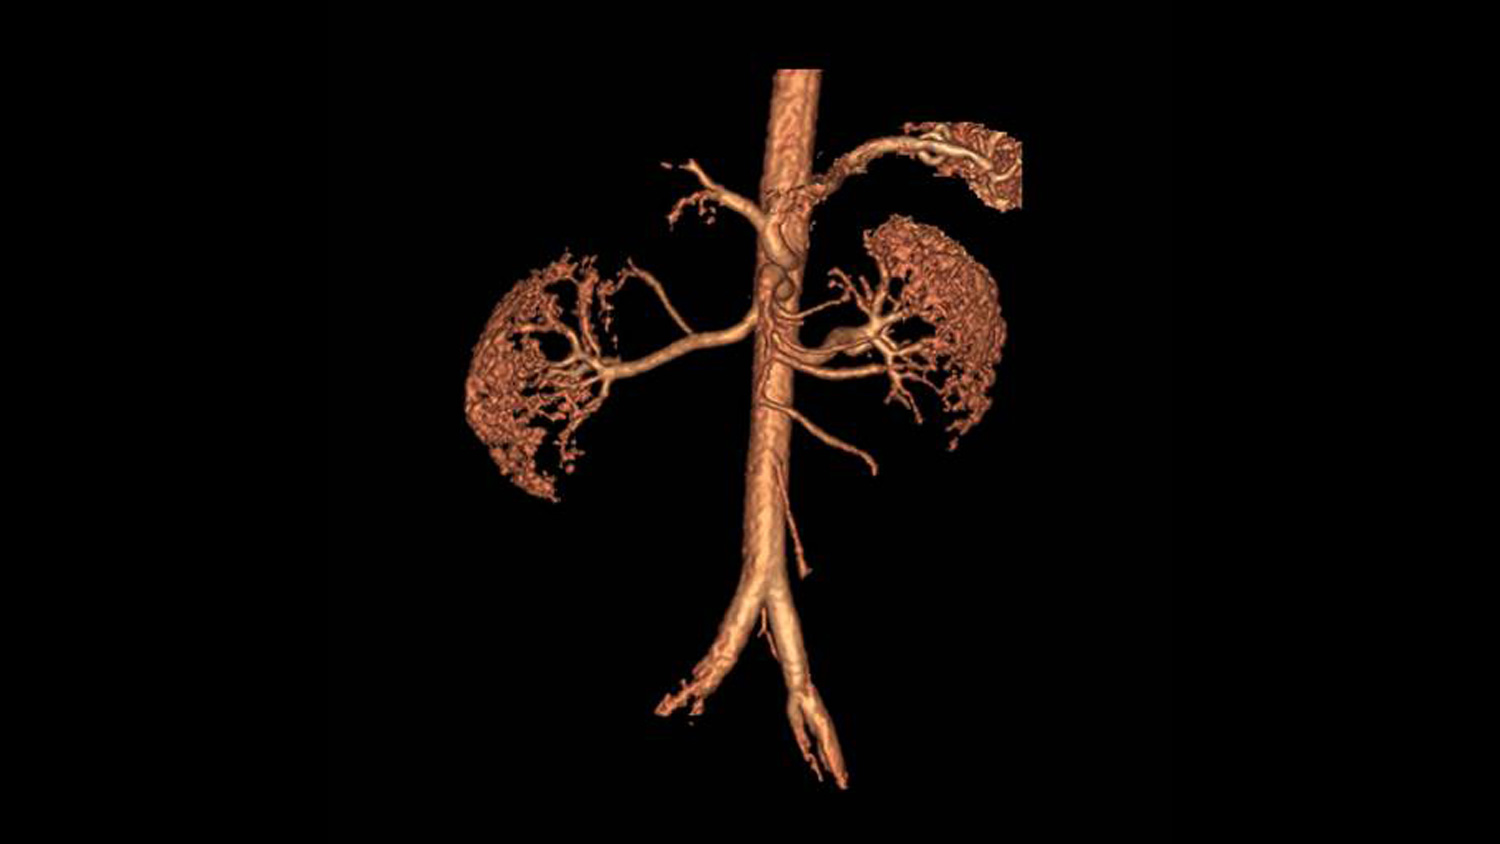

Evaluar el diagnóstico de estenosis de arteria renal mediante Angiografía por Resonancia Magnética sin ningún medio de contraste, es posible gracias a nuestro nuevo equipo de Resonancia magnética la cual cuenta con 1.5 teslas y es totalmente digital. Los estudios se realizan en menor tiempo y con una calidad de imagen insuperable

Ahora es posible realizar una angiografía a los pacientes con patologías renales sin necesidad de aplicar gadolinio y más importante sin sacrificar la calidad del estudio. La imagen es generada en alta definición (HD) y en reconstrucción 3D se puede ver a detalle de la anotomia renal del paciente. Con nuestra aplicación Inhance Suite 2.0 es posible visualizar el flujo arterial y venoso gracias a una avanzada gama de potentes y sólidas secuencias de pulso y sin necesidad de administrar contrastes de gadolinio.

Inhance es una técnica de angiografía sin realce de contraste por RM desarrollada para adquirir imágenes de las arterias y suprimir el tejido estacionario y el flujo venoso de fondo. Esta secuencia proporciona una excelente relación señal-ruido (SNR) y genera imágenes de sangre blanca. Se aplican pulsos selectivos de inversión sobre la región de interés para invertir el tejido arterial, venoso y estacionario. En el punto nulo de los tejidos de fondo, se aplica un pulso de excitación para generar la señal. El resultado neto es una imagen angiográfica con una excelente supresión de la señal de fondo y libre de contaminación venosa. La técnica selectiva de saturación espectral química (SPECIAL) le permite lograr una supresión uniforme de grasa, mientras que la compatibilidad con el gating respiratorio reduce los artefactos provocados por el movimiento respiratorio durante las exploraciones renales en respiración libre.

Nos permite adquirir imágenes angiográficas de las arterias cerebrales y renales con una excelente supresión de la señal de fondo en un reducido tiempo de exploración. Mediante la adquisición de imágenes volumétricas 3D de contraste de fase combinadas con imagen en paralelo, un eficaz muestreo del espacio k y la optimización de las secuencias de pulso, es capaz de registrar toda la anatomía neurovascular en aproximadamente cinco a seis minutos. Además, la supresión de la señal de fondo mejora gracias al diseño optimizado de la secuencia de pulso, lo que contribuye a una visualización detallada de las ramas de menor tamaño. La técnica de adquisición de señales sincronizada con el ciclo respiratorio (respiratory triggering) también es compatible con Inhance 3D Velocity, lo que permite llevar a cabo angiografías abdominales, especialmente de las arterias renales. El resultado es una productividad y calidad de imagen excepcionales.

Todas estas novedosas aplicaciones de Resonancia magnética nos permiten que sin realce de contraste se obtengan imágenes de las arterias periféricas. Está basada en secuencias 3D FSE con sincronismo cardiaco y adquiere dos ecos, uno en fase diastólica y otro en fase sistólica. La lentitud del flujo arterial durante la fase diastólica se traduce en arterias de sangre blanca en las imágenes diastólicas, mientras que el flujo arterial más rápido durante la fase sistólica resulta en arterias de sangre negra en las imágenes sistólicas. La sustracción de imágenes sistólicas de las imágenes diastólicas proporciona imágenes exclusivamente arteriales con una supresión excelente de la señal venosa y la señal de fondo. Adquisición entrelazada y con imagen en paralelo (ASSET) con una trayectoria optimizada del espacio k ayuda a reducir el registro de movimiento y a mejorar la visualización de los vasos respectivamente. Además, la adquisición de imágenes con transformada de Fourier parcial y de planos coronales permite reducir considerablemente el tiempo de exploración.

Además una secuencia de pulso nos ayuda a adquirir imágenes angiográficas de las arterias que permanecen relativamente rectas (es decir, la arteria femoral, poplítea y carótida). El flujo sanguíneo arterial se acelera durante la fase sistólica y se ralentiza durante la fase diastólica. Con la ventaja de que se pueden obtener datos durante la fase sistólica. Ofrece una brecha de saturación espacial optimizada para mejorar la supresión de grasa y la señal de fondo. Se reducen al mínimo los artefactos producidos por el flujo pulsátil. Además es compatible con imagen paralela ( ASSET) para reducir los tiempos de exploración.